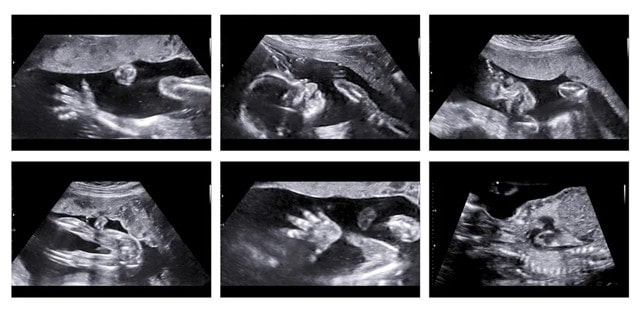

胎动指的是胎儿在子宫腔里的活动冲击到子宫壁的动作。胎儿在子宫内伸手、踢腿、冲击子宫壁,这就是胎动。

胎儿在子宫内的胎动大致可以分为4种类型:全身心运动、肢体性运动、下肢运动、胸壁运动。